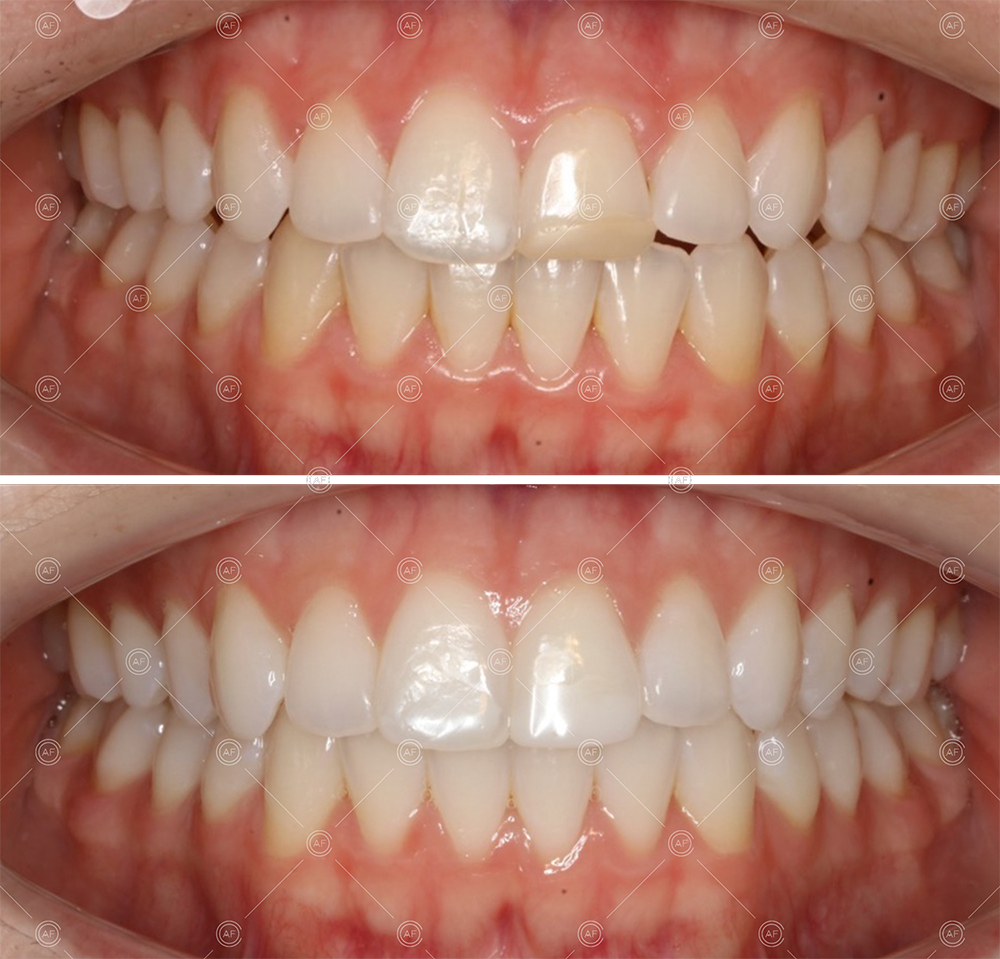

MH debonded in December 2020, with overall treatment time of around 14 months.

She was provided with upper and lower vacuum form retainers, and asked to wear these every night for the first year, and alternate nights for the second year onwards, indefinitely for as long as she wanted her teeth to remain straight. High quality finish was maintained at one year post-debond.